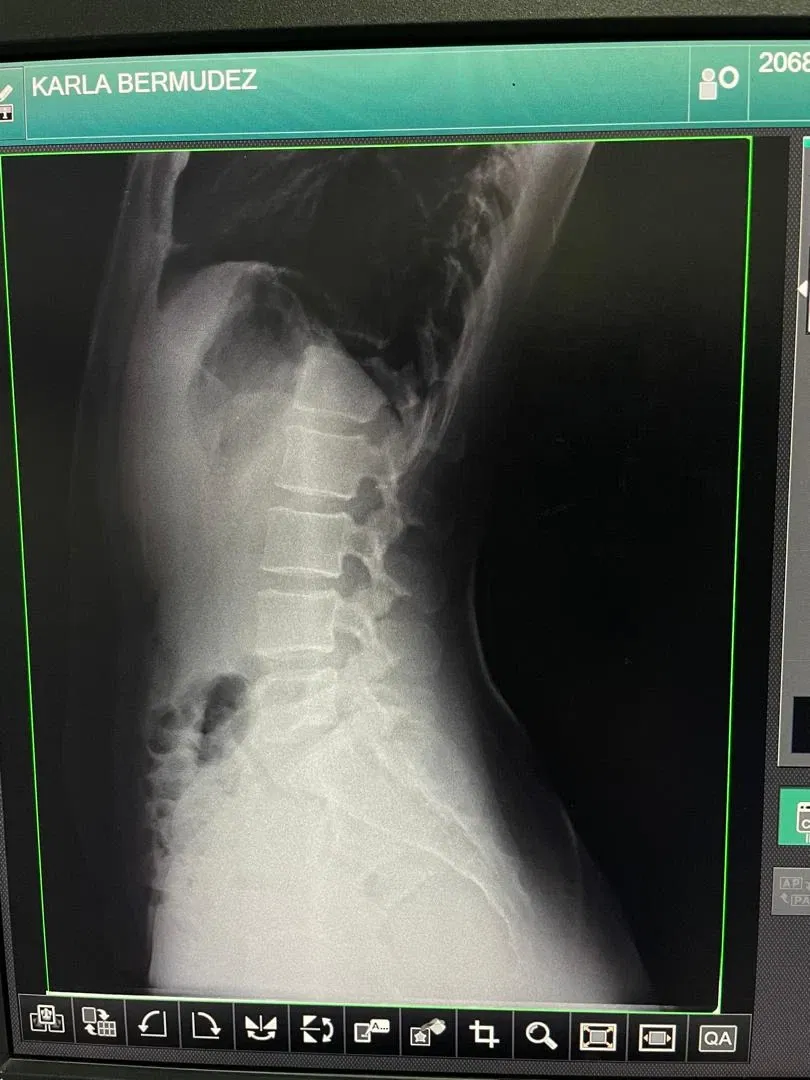

Desde hace 6 semanas comencé con un dolor en el femoral, pensando que era el músculo contraído, desde entonces por la intensidad del dolor, he asistido a ambulatorios, el seguro social, clínicas y hospital, todo para dar un diagnóstico... Exámenes de laboratorio, rayos X, y muchos tratamientos en eso ha transcurrido mis días desde entonces 😓

Al final de todo me refirieron a neurocirugía 😱🥺cosa que me alarmó mucho, sin embargo, con mucha tranquilidad fui a consulta, confiando que no sea nada quirúrgico... Y bueno, aún no tenemos un diagnóstico certero, pues me ordenaron realizar un Rx dinámica de la columna lumbosacra y una resonancia magnética de esa zona para así poder dar un buen diagnóstico y el tratamiento y rehabilitación adecuada.

Six weeks ago, I started having pain in my femoral artery, thinking it was a contracted muscle. Since then, due to the intensity of the pain, I've been to outpatient clinics, social security, clinics, and the hospital, all trying to get a diagnosis... Lab tests, X-rays, and many treatments have been what I've been doing ever since. 😓

In the end, they referred me to neurosurgery, which alarmed me greatly. However, I calmly went to the consultation, confident that it wouldn't be anything surgical... And well, we still don't have a definitive diagnosis, so they ordered a dynamic X-ray of the lumbosacral spine and an MRI of that area to be able to give a good diagnosis and the appropriate treatment and rehabilitation.